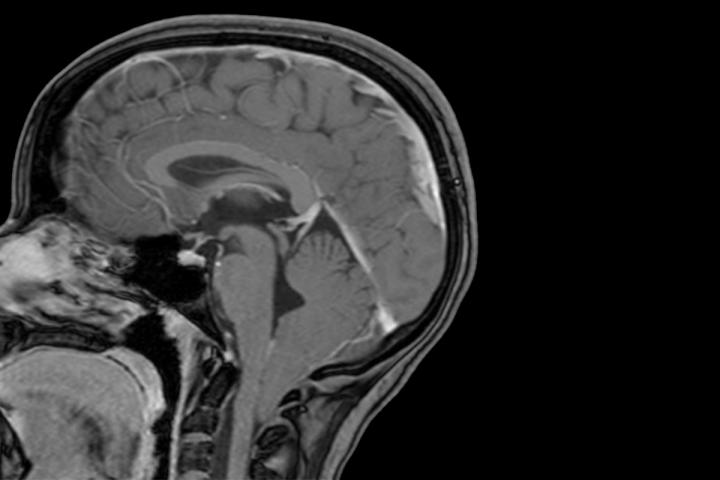

image: The lowest part of a child's brain is visible below the bottom of the skull in this MRI scan and shows evidence of a Chiari 1 malformation. Researchers at Washington University School of Medicine in St. Louis have shown that Chiari 1 malformation can be caused by variations in two genes linked to brain development, and that children with large heads are at increased risk of developing the condition.

The condition occurs when the lowest parts of the brain are found below the base of the skull. The study also revealed that children with unusually large heads are four times more likely to be diagnosed with Chiari 1 malformation than their peers with normal head circumference.